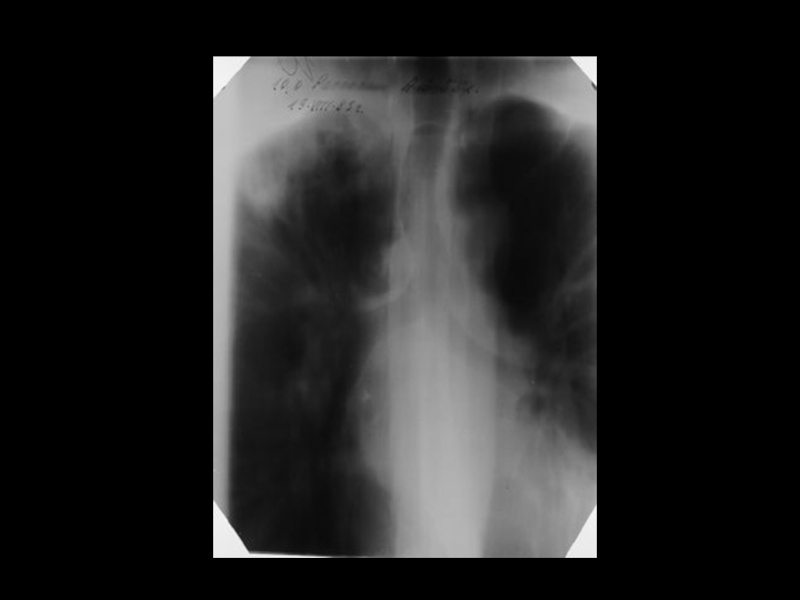

Центральный рак легкого

ЛУЧЕВАЯ ДИАГНОСТИКА РАКА ЛЕГКОГО